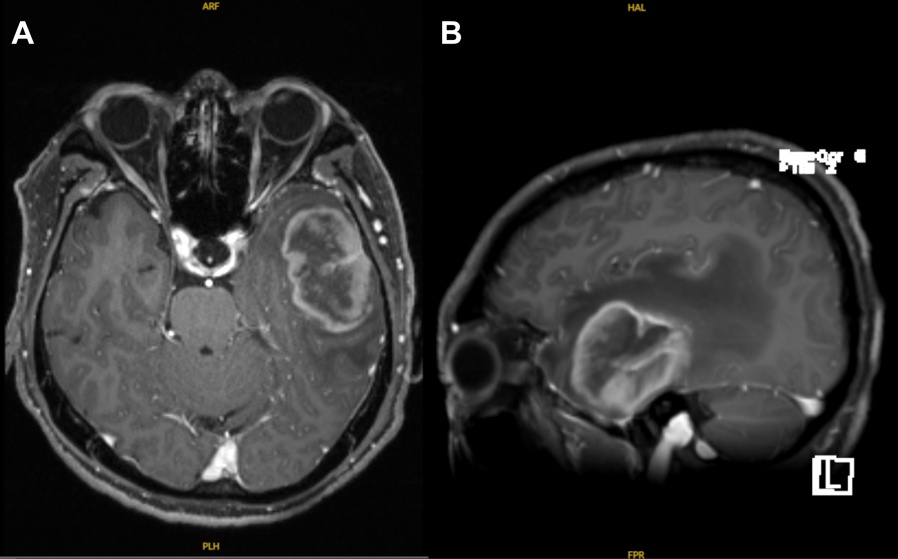

患者主诉为头痛20余天,记忆力减退伴言语不清2天。20余天前无明显诱因出现头痛,伴头晕,伴恶心、呕吐数次,呕吐物为胃内容物,2天前患者出现记忆力减退,伴命名性失语,伴右侧口角歪斜、口角流涎,伴双手麻木,无四肢活动障碍,查颅脑CT示左侧颞叶占位,符合脑肿瘤表现,患者平素身体健康,无其他疾病,“蚕蛹”过敏史。吸烟史40年,每日40支,饮酒史40年,偶有饮酒。体格检查:神志清,言语欠流利,命名性失语,右侧鼻唇沟浅,其余查体未见明显异常。辅助检查:入院颅脑CT平扫显示左侧颞叶占位性病变,符合胶质瘤的影像表现,术前颅脑MR (图1)平扫及增强结果显示同样的结果。于我院行神经导航联合黄荧光下左侧额颞开颅脑肿瘤切除术,术中见肿瘤位于左侧颞叶皮层下,肿瘤质韧,血运丰富,边界不清,荧光辅助下分块全切肿瘤,术区彻底止血。术后行常规病理及免疫组化检测。

Figure 1. Magnetic resonance imaging (MRI): (A) axial T1-weighted MPRAGE fat-suppressed sequence; (B) sagittal multiplanar reconstruction (MPR) thick-slab image

1. 磁共振成像:(A) 轴位T1加权MPRAGE脂肪抑制序列;(B) 矢状位MPR厚层重建图像

PCNSL的均质性显著强化与GBM的不均质、不规则环形强化是两者最直观的鉴别点[3]。根据Malikova等人对108例确诊患者的对比研究的研究,PCNSL表现出显著的形态学一致性,增强MRI中高达64.8%的病灶呈现典型的均质性强化[4];与鱼博浪提到的PCNSL CT密度和MR信号较为均匀的特征相符[3]。相比之下,GBM呈现出极高的肿瘤异质性,98.1%的病例表现为不均匀花环状强化,且绝大多数伴有肉眼可见的坏死[4] [5],而PCNSL若无免疫缺陷背景,极少出现坏死(仅5.6%) [4]。本例患者,在MR增强上虽然病灶整体表现为不均质的花环状强化,极度类似于胶质母细胞瘤,但在病灶部分区域(如内部边缘区域)仍表现出PCNSL的典型特点即实质均匀一致强化,这与GBM不同,后者的环壁常表现为明显不均质强化的信号特点。